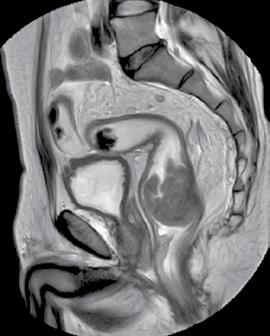

Deși CT-ul este deosebit de util în evaluarea metastazelor, imagistica prin rezonanță magnetică (IRM) reprezintă standardul de aur pentru examinarea detaliată a extensiei loco-regionale în cazul tumorilor rectale (stadiul T). IRM-ul pel vin permite o caracterizare precisă a tumorii primare și a invaziei acesteia în structurile adiacente, precum grăsimea mezorectală, fascia mezorectală, peritoneul, aparatul sfincterian, vezica urinară sau organele genitale. De asemenea, este

Tumoră rectală. Examen IRM, secvența T2 ponderată, plan sagital.

Din colecția Centrului de Imagistică, UMFCV

excelent pentru identificarea ganglionilor limfatici afectați (stadiul N), precum și în identificarea altor markeri cu valoare prognostică (invazia vasculară extramurală, depozitele tumorale ș.a.).

Protocolul de examinare prin IRM în cancerul rectal implică o serie de pași pregătitori, indicați pentru a asigura o vizualizare optimă a pereților rectali, lipsită de artefacte. Aceștia includ efectuarea unei microclisme pentru a goli lumenul rectal de resturi fecale, administrarea de spasmolitice (ex. Buscopan) pentru reducerea mișcărilor peristaltice și, eventual, administrarea intrarectală de apă sau gel. Examinarea propriu-zisă durează, în medie, 30-45 de minute și include secvențe T2 ponderate, realizate în mai multe planuri, pentru evaluarea detaliată a tumorii și a extensiei locale, dar și secvențe de difuzie și secvențe cu contrast dinamic pentru o caracterizare suplimentară a biologiei tumorii.